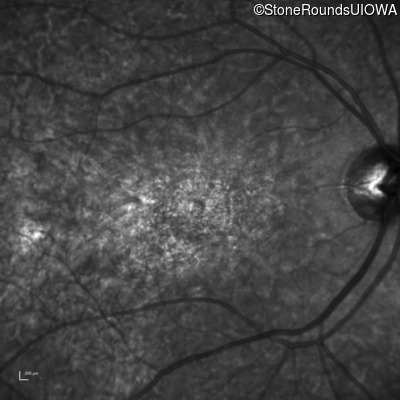

The clinical features favoring the diagnosis of ABCA4-associated autosomal recessive Stargardt disease in this patient include: loss of acuity at the beginning of the second decade, parafoveal photoreceptor loss on OCT, pisciform flecks in the macula with clear peripapillary sparing, and normally sighted parents.

All three of the cardinal ophthalmic features of Mendelian macular dystrophies are present in this patient. The most striking features of the fundus exam are the numerous yellow flecks at the level of the RPE. Flecks are most commonly seen in AR Stargardt disease and pattern dystrophy although they may be seen in some of the rarer Mendelian maculopathies as well. The visual acuity in patients with AR Stargardt disease is often "worse than the fundus looks" while the acuity in pattern dystrophy is often quite good despite extensive flecks. The pedigree of this patient is compatible with ABCA4-associated Stargardt disease and the better than expected acuity is attributable to foveal sparing (see below). The onset of reduced acuity at age 10 is much more characteristic of ABCA4 disease than pattern dystrophy. Another feature present in this patient that is very frequently seen in Stargardt disease is peripapillary sparing. However, this sign can be seen in pattern dystrophy as well. When central atrophy is present in ABCA4-associated Stargardt disease it often somewhat shiny (which is uncommon with the geographic atrophy of pattern dystrophy or age-related macular degeneration). Some patients with ABCA4-associated Stargardt disease can have some preservation of the fovea giving a zonal "bullseye" appearance to the center of the macula. Sometimes this preservation is associated with preserved acuity as in this case. The outer nuclear layer (ONL) is much thinner than normal on OCT, indicative of photoreceptor loss. This is associated with a thinning of the ellipsoid zone which is usually many times brighter and thicker than the external limiting membrane (ELM). These two lines are essentially equal in intensity in this patient. The foveal sparing is seen on OCT only as a small bit of retinal convexity in the center of the atrophy coupled with a small bit of residual RPE flanked by bare Bruch's membrane. The presence of a robust I2e isopter on Goldmann perimetry places this patient in the least severe half of all Stargardt patients (see Schindler, et al., 2010). Most patients with ABCA4-associated disease are somewhat myopic as is this patient. Stargardt patients also tend to perform very poorly on pseudoisochromatic plates, even when their acuity is still fairly good as it is here.